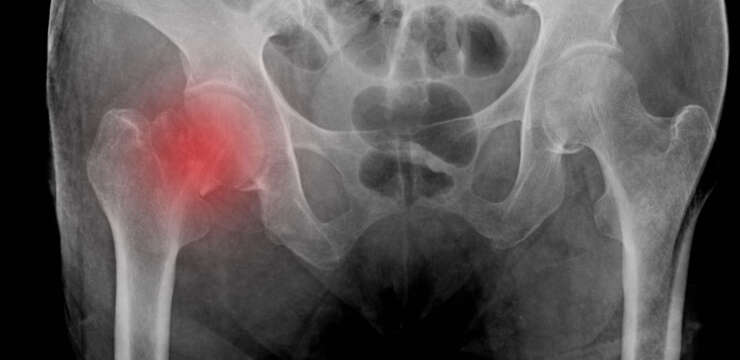

Ciddi yaralanmalar, kemik kırıkları veya bağ yaralanmaları protez gerektirebilir. Diz kemiği üzerindeki kan akışının bozulması sonucu kemik dokusunun ölümüne (aseptik nekroz) yol açabilir. Bu durumda diz protezi gerekebilir. İltihaplı durumlar veya enfeksiyonlar eklemde hasara yol açabilir ve ameliyat gerekebilir.